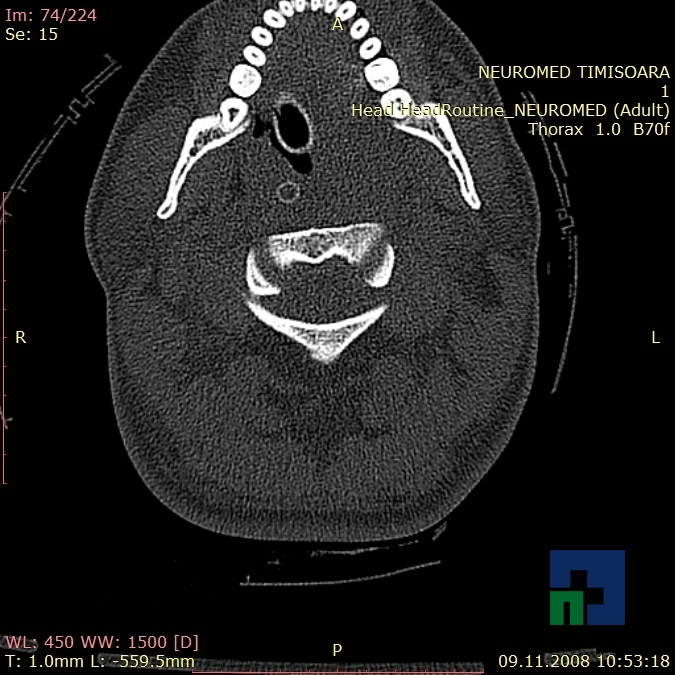

- Accidentelor vasculare cerebrale ischemice sau hemoragice

- Tumorilor cerebrale:

- Empiemul subdural

- Abcesul cerebral

- Fistula carotido-cavernoasa

- Higroma

- Atrofia cerebrală regională